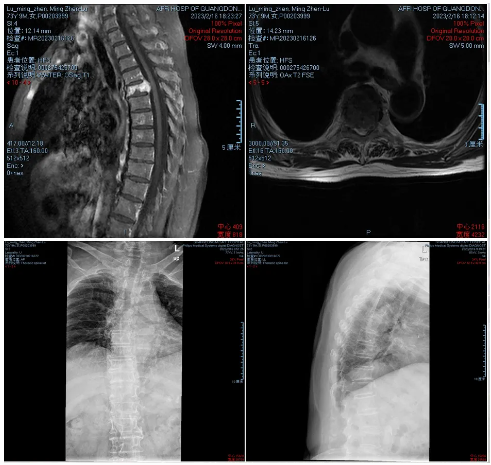

·患者陆某某,女,73岁,因反复胸背部疼痛1年余入院。胸背痛VAS评分7分。

·诊断:胸4椎体浆细胞骨髓瘤

射频消融治疗后疼痛缓解明显,术后第二天即可佩戴腰围起床活动,胸背痛VAS评分2分。